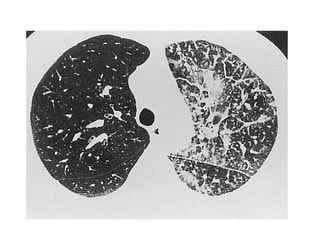

e) Desquamative Interstitial Pneumonia (DIP) : Diffuse

ground-glass

-At high-resolution CT, DIP is characterized by diffuse

ground-glass opacities

-Usually, there is a peripheral and lower lung lobe

predominance

-Other frequent CT findings include spatially limited

irregular linear opacities and small cystic spaces, which

are indicative of fibrotic changes